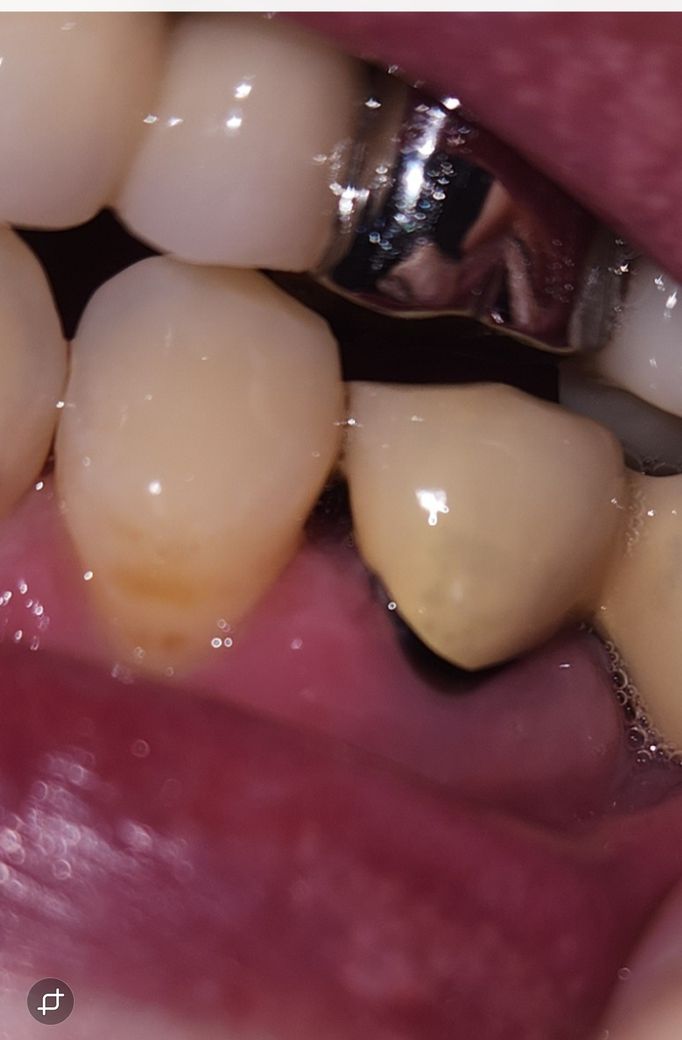

치주염 치과의사 선생님 계실까요~?

다름이 아니오라 예전에 신경치료후 크라운으로 덮어 씌웠습니다.

하지만 앞자연치아의 공간 사이와 크라운치아가 조금 벌어져있게 제작되었습니다.

그래서 저 사이의 공간이 좀 있는편이라 거기에 음식물 찌꺼기가 많이 끼는 편입니다.

이에 치실을 하루 한번 하는편인데, 잇몸이 조금 내려가는 기분이 들어서 이렇게 사진을 올리게 되었습니다.

혹시 치주염인지 봐주실 치과의사 선생님 계실까요..? ㅠㅠ..

• 1번 째 사진

해당 부위에서 출혈이나 농이 나온다면 치주염을 의심해볼 수 있습니다. 잇몸에 붓기 등은 있어보입니다.

보철물을 만들떄 무조건 치아 사이를 완전히 메꾸는건 아닙니다. 아마 처음에는 저정도 공간은 아니엿지만 시간이 지나면서 잇몸이 내려가면서 공간이 더 넓어진거 같습니다.

현재로써는 잇몸이 많이 내려와 있어보이지는 않으나, 이 공간이 음식물 찌꺼기로 인해 염증을 유발될수 있습니다.